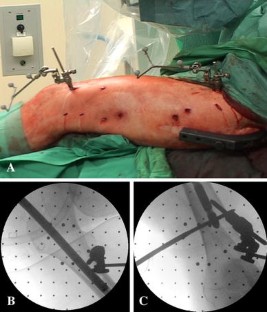

Fig. 2